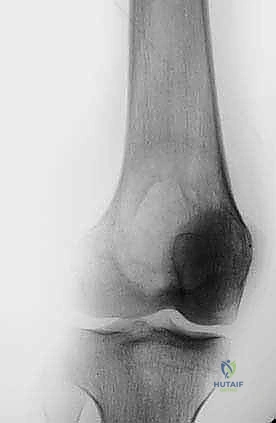

حتى الأورام الحميدة، مثل الورم ذو الخلايا العملاقة (Giant Cell Tumor) أو الأورام الغضروفية (Chondroblastoma)، يمكن أن تكون "عدوانية محلياً". هذا يعني أنها تنمو وتأكل العظم المحيط بها، مما يضعف الهيكل العظمي ويؤدي إلى كسور مرضية، ويهدد بانهيار المفصل القريب. هنا يكمن التحدي: كيف نزيل الورم بالكامل دون تدمير العظم السليم المتبقي؟

- التورم والكتل: ظهور تورم ملحوظ أو كتلة صلبة محسوسة فوق العظم أو بالقرب من المفصل.

- الكسور المرضية: كسر العظم نتيجة إصابة بسيطة جداً لا تسبب عادة كسوراً للأشخاص الأصحاء.